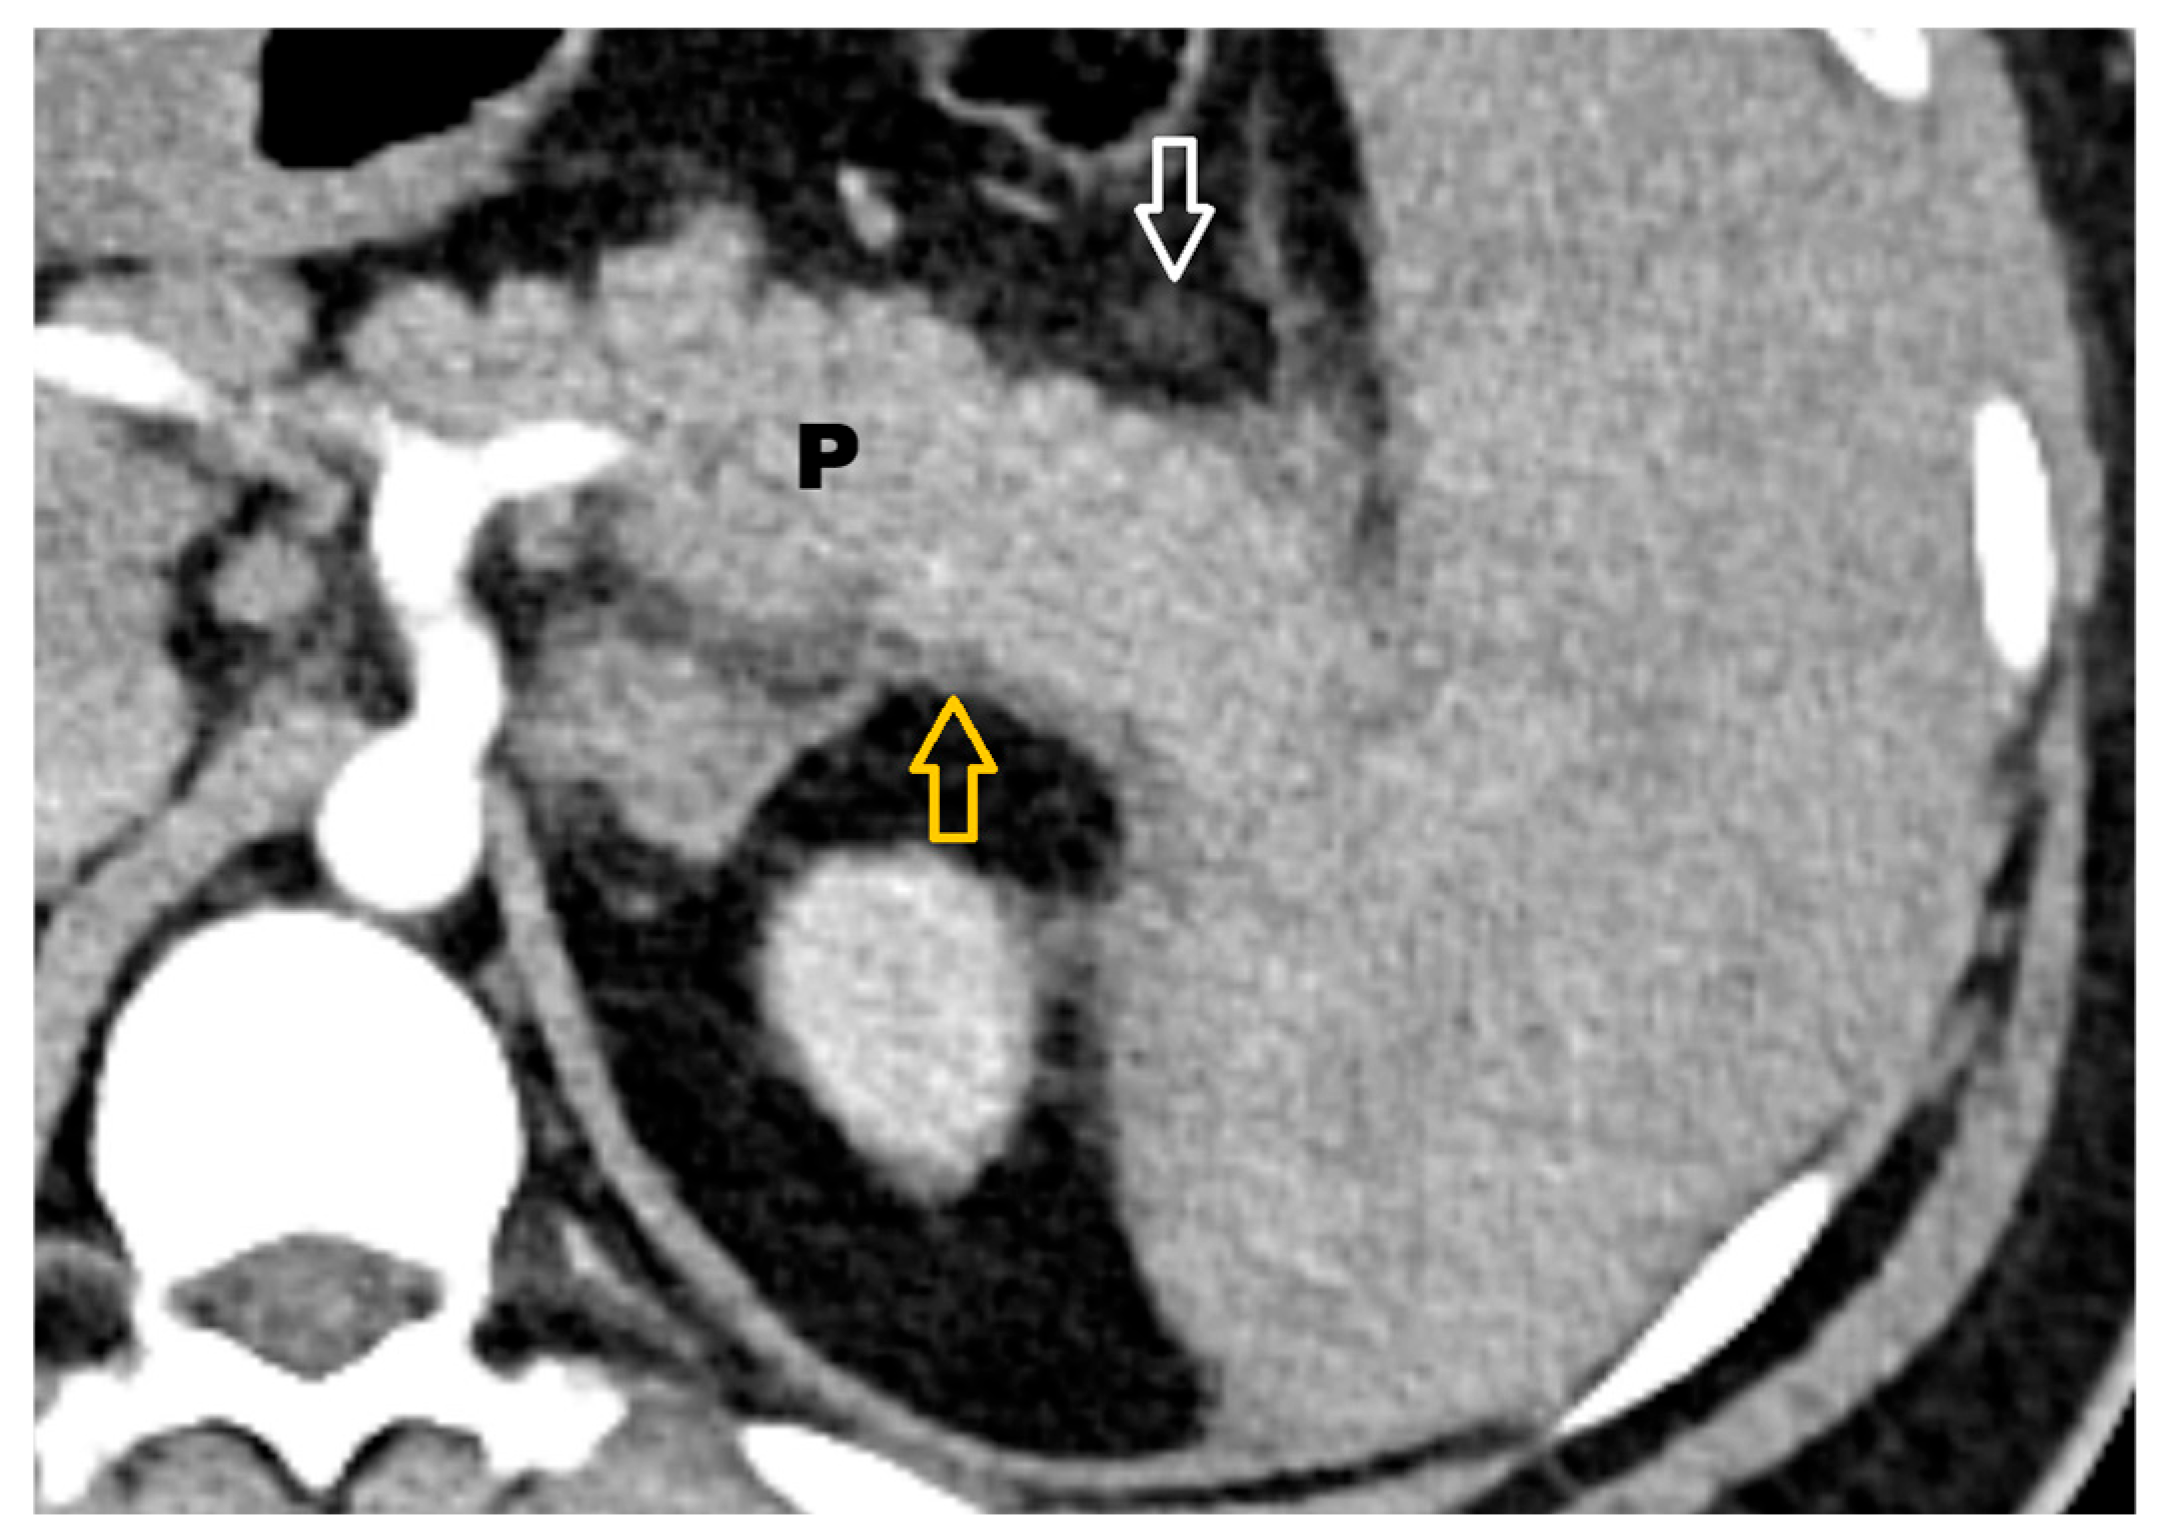

- diffuse or focal enlargement of the pancreas → 1;

- minimal peripancreatic changes → 2;

- single peripancreatic fluid collection → 3;